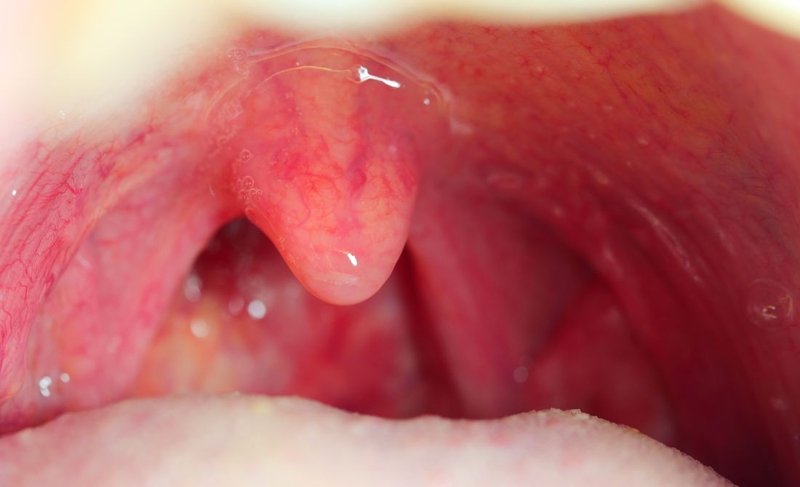

Amidan là khối mô bạch huyết nằm ở hai bên thành họng, đóng vai trò như hàng rào miễn dịch đầu tiên, giúp ngăn vi khuẩn và virus xâm nhập cơ thể bằng cách sản xuất kháng thể. Amidan hoạt động mạnh ở trẻ em nhưng dễ bị viêm, gây đau họng và sốt.

Về mặt giải phẫu, amidan là các tổ chức lympho, chứa nhiều tế bào bạch cầu. Thông thường, chúng ta ít để ý đến amidan nhưng nó lại đóng vai trò vô cùng quan trọng trong hệ miễn dịch của cơ thể. Giống như những “chiến binh thầm lặng”, amidan luôn sẵn sàng chống lại các tác nhân gây bệnh xâm nhập vào cơ thể qua đường hô hấp.

Viêm amidan là tình trạng viêm nhiễm xảy ra khi amidan bị tấn công bởi vi khuẩn hoặc virus, như liên cầu khuẩn nhóm A, virus cúm hoặc virus cảm lạnh. Các tác nhân gây bệnh này có thể lây qua đường hô hấp khi người bệnh tiếp xúc gần gũi với người nhiễm bệnh hoặc do thời tiết thay đổi và không khí lạnh. Dấu hiệu của viêm amidan bao gồm đau họng, sốt cao, khó nuốt. Amidan sưng to, đỏ, có thể có mảng mủ trắng. Ngoài ra, người bệnh còn có thể bị hôi miệng do nhiễm trùng.

Amidan phì đại xảy ra khi amidan bị viêm nhiễm nhiều lần hoặc viêm mạn tính, khiến chúng phát triển và phình to. Tình trạng này có thể gây ảnh hưởng lớn đến đường hô hấp. Đặc biệt là khi amidan phì đại làm tắc nghẽn đường thở, gây khó khăn trong việc thở và ngáy to khi ngủ. Amidan lớn làm hẹp đường thở có thể gây ngưng thở khi ngủ. Ngoài ra, amidan phì đại còn ảnh hưởng đến khả năng nuốt thức ăn và nước.